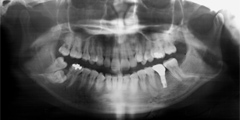

食事中に前歯がいきなりグラグラとしだした

食事中に前歯がぐらぐらしてきて、最初のころは、しばらく放っておいたそうですが、しばらくすると、前歯がついに折れてしまったということです。

患者様が吉本歯科医院に来院された時には、その他の歯もグラグラになっている部分があることが診断でわかりました。患者さまの自覚症状としては、「とにかく前歯をくっつけて欲しい」ということでした。

噛み合わせが非常に悪く、上の歯が下の歯にすっぽりと覆いかぶさっておりまともに噛めていない状態であることがわかりました。

・もともとの咬合不全(噛み合わせ(咬み合わせ)の悪さ)による前歯の破折

・歯を支える骨も溶けて薄くなってしまっている状態